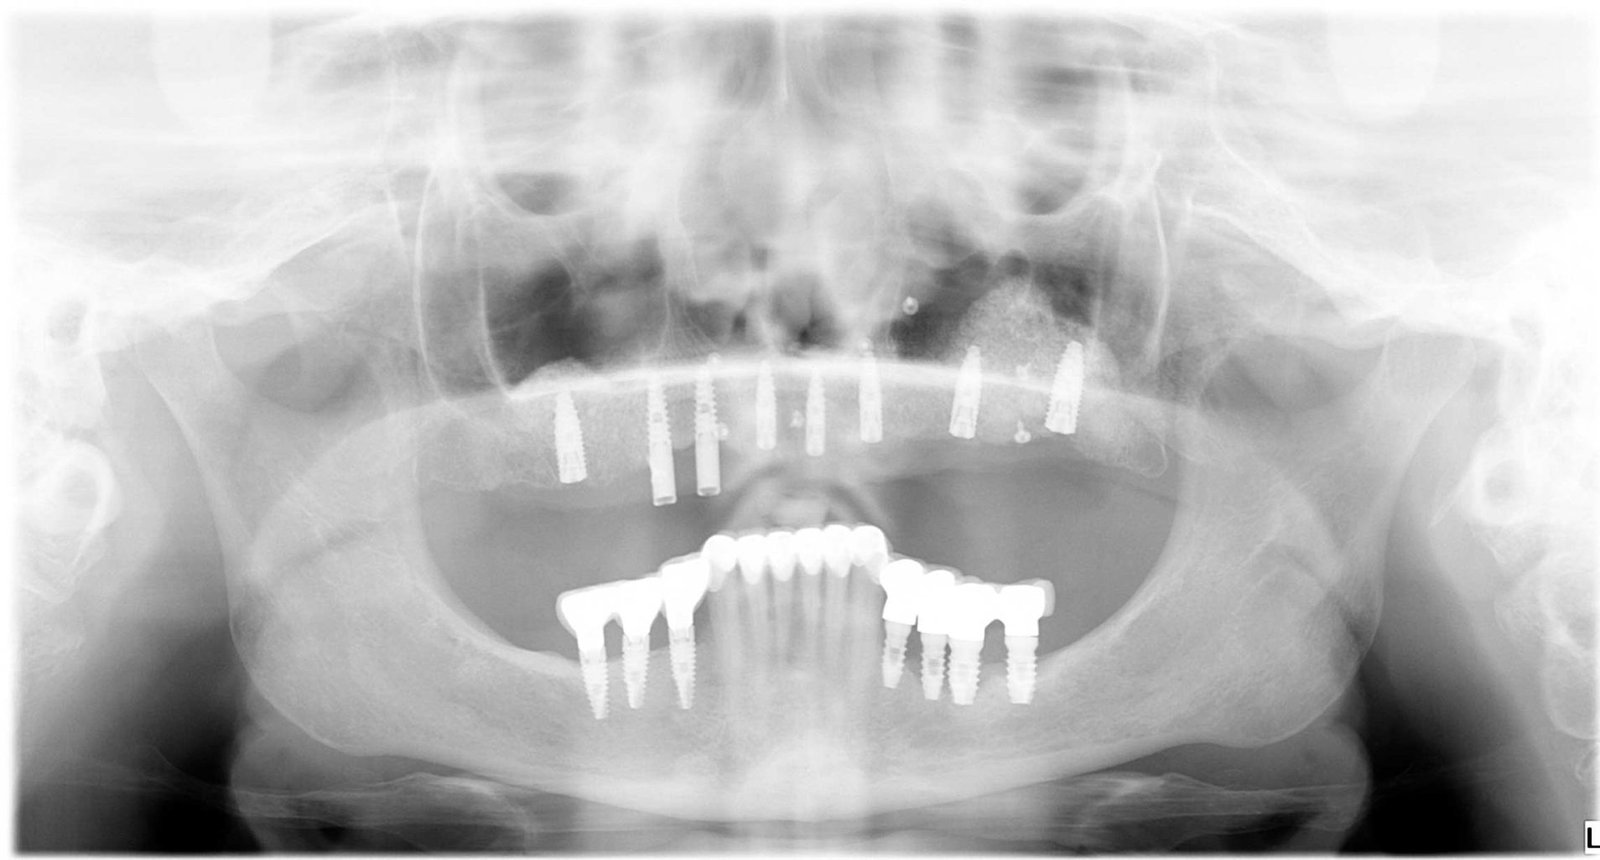

Caso 2 - caso de Implantes dentales

El paciente presentaba pérdidas dentales que comprometían tanto la función como la estabilidad de su mordida. Mediante un tratamiento con implantes personalizados logramos restablecer una dentadura fija, estable y adaptada a su anatomía.

Se observa la colocación de los implantes en la posición óptima, garantizando una base sólida para la posterior rehabilitación protésica.

La radiografía final confirma la correcta integración de los implantes, asegurando una solución duradera y completamente funcional.